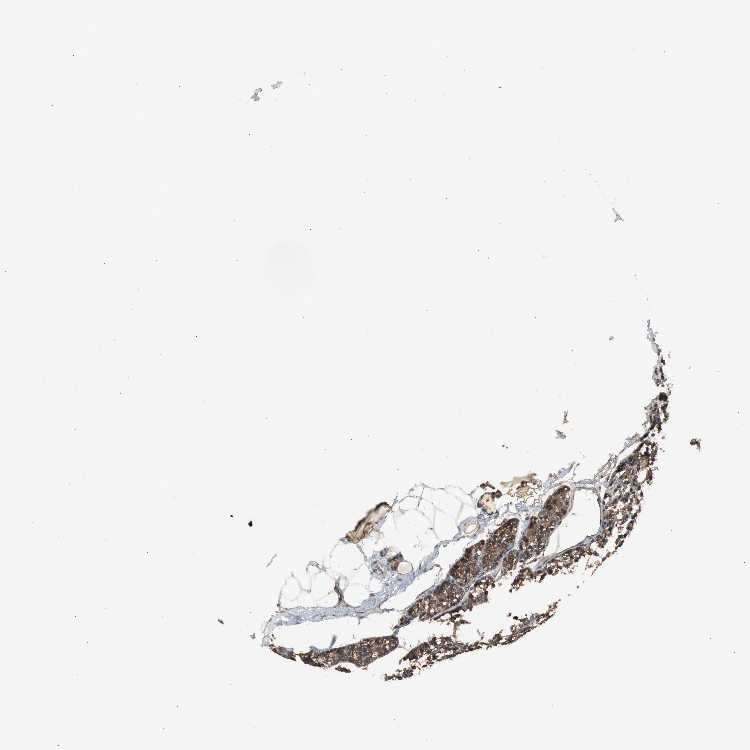

PARATHYROID GLAND - Antibody stainingi

Antibody staining in the annotated cell types in the current human tissue is reported as not detected, low, medium, or high, based on conventional immunohistochemistry profiling in selected tissues. This score is based on the combination of the staining intensity and fraction of stained cells.

Each image is clickable and will lead to virtual microscopy that enables deeper exploration of all samples and also displays staining intensity scores, fraction scores and subcellular localization as well as patient and tissue information for each sample.

Antibody HPA006872

Glandular cells High